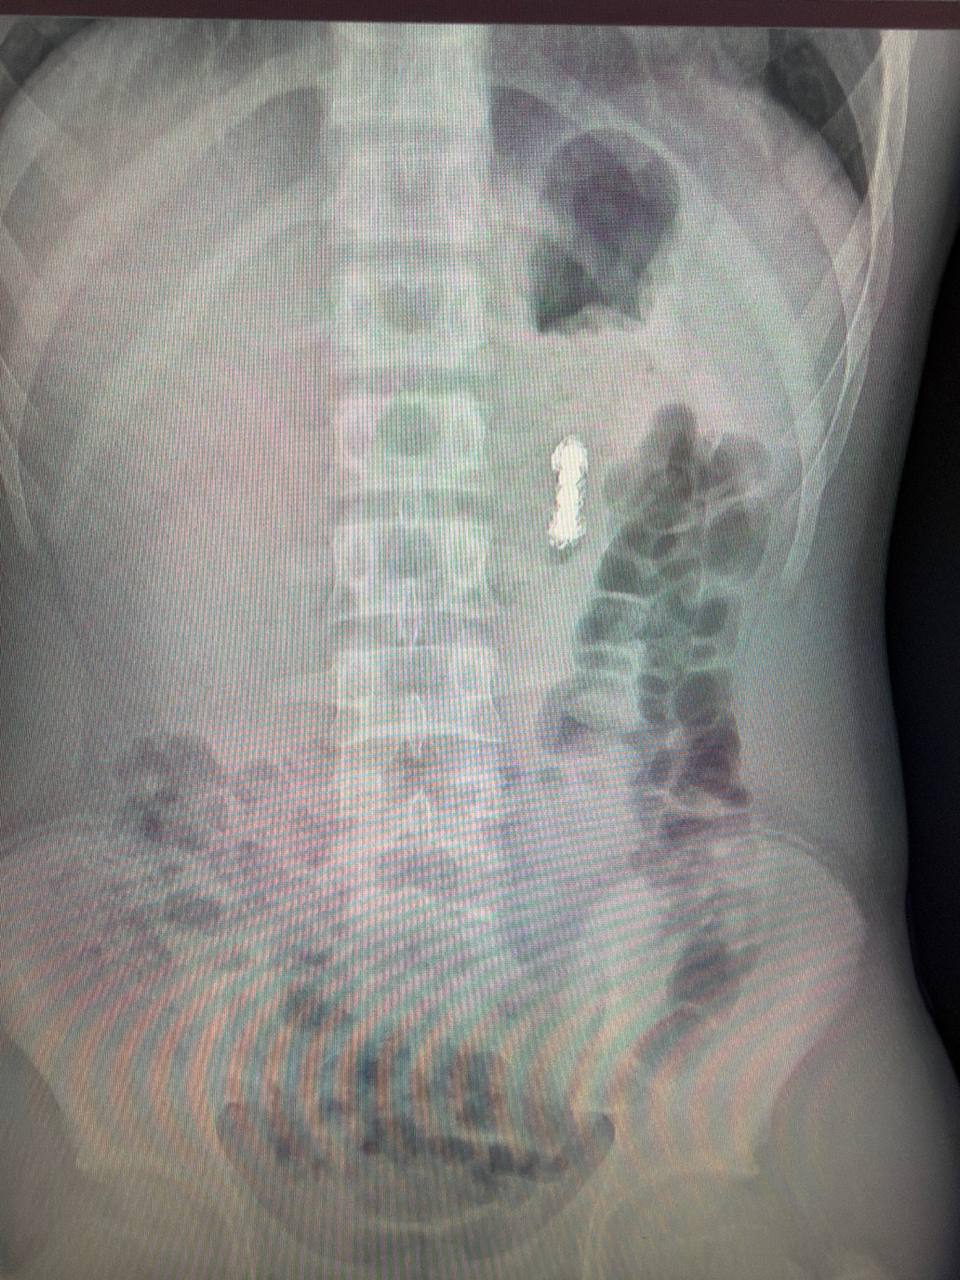

Позвоночник оказался в порядке, но на снимке заметили инородные предметы в желудочно-кишечном тракте. Выяснилось, что это магниты.

В Центре Рошаля врачи обнаружили семь магнитов в желудке и еще четыре — дальше по кишечнику. Со временем они сцепились между собой и повредили стенку желудка.

Сначала медики эндоскопически извлекли семь магнитов, а затем провели полостную операцию и достали оставшиеся четыре из тонкой кишки.